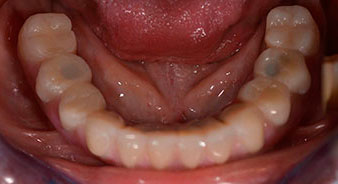

La patiente âgée de 64 ans présente une denture résiduelle des dents 38, 33 et 43 et une prothèse amovible mandibulaire stabilisée par crochets (Fig. 1 et 2).